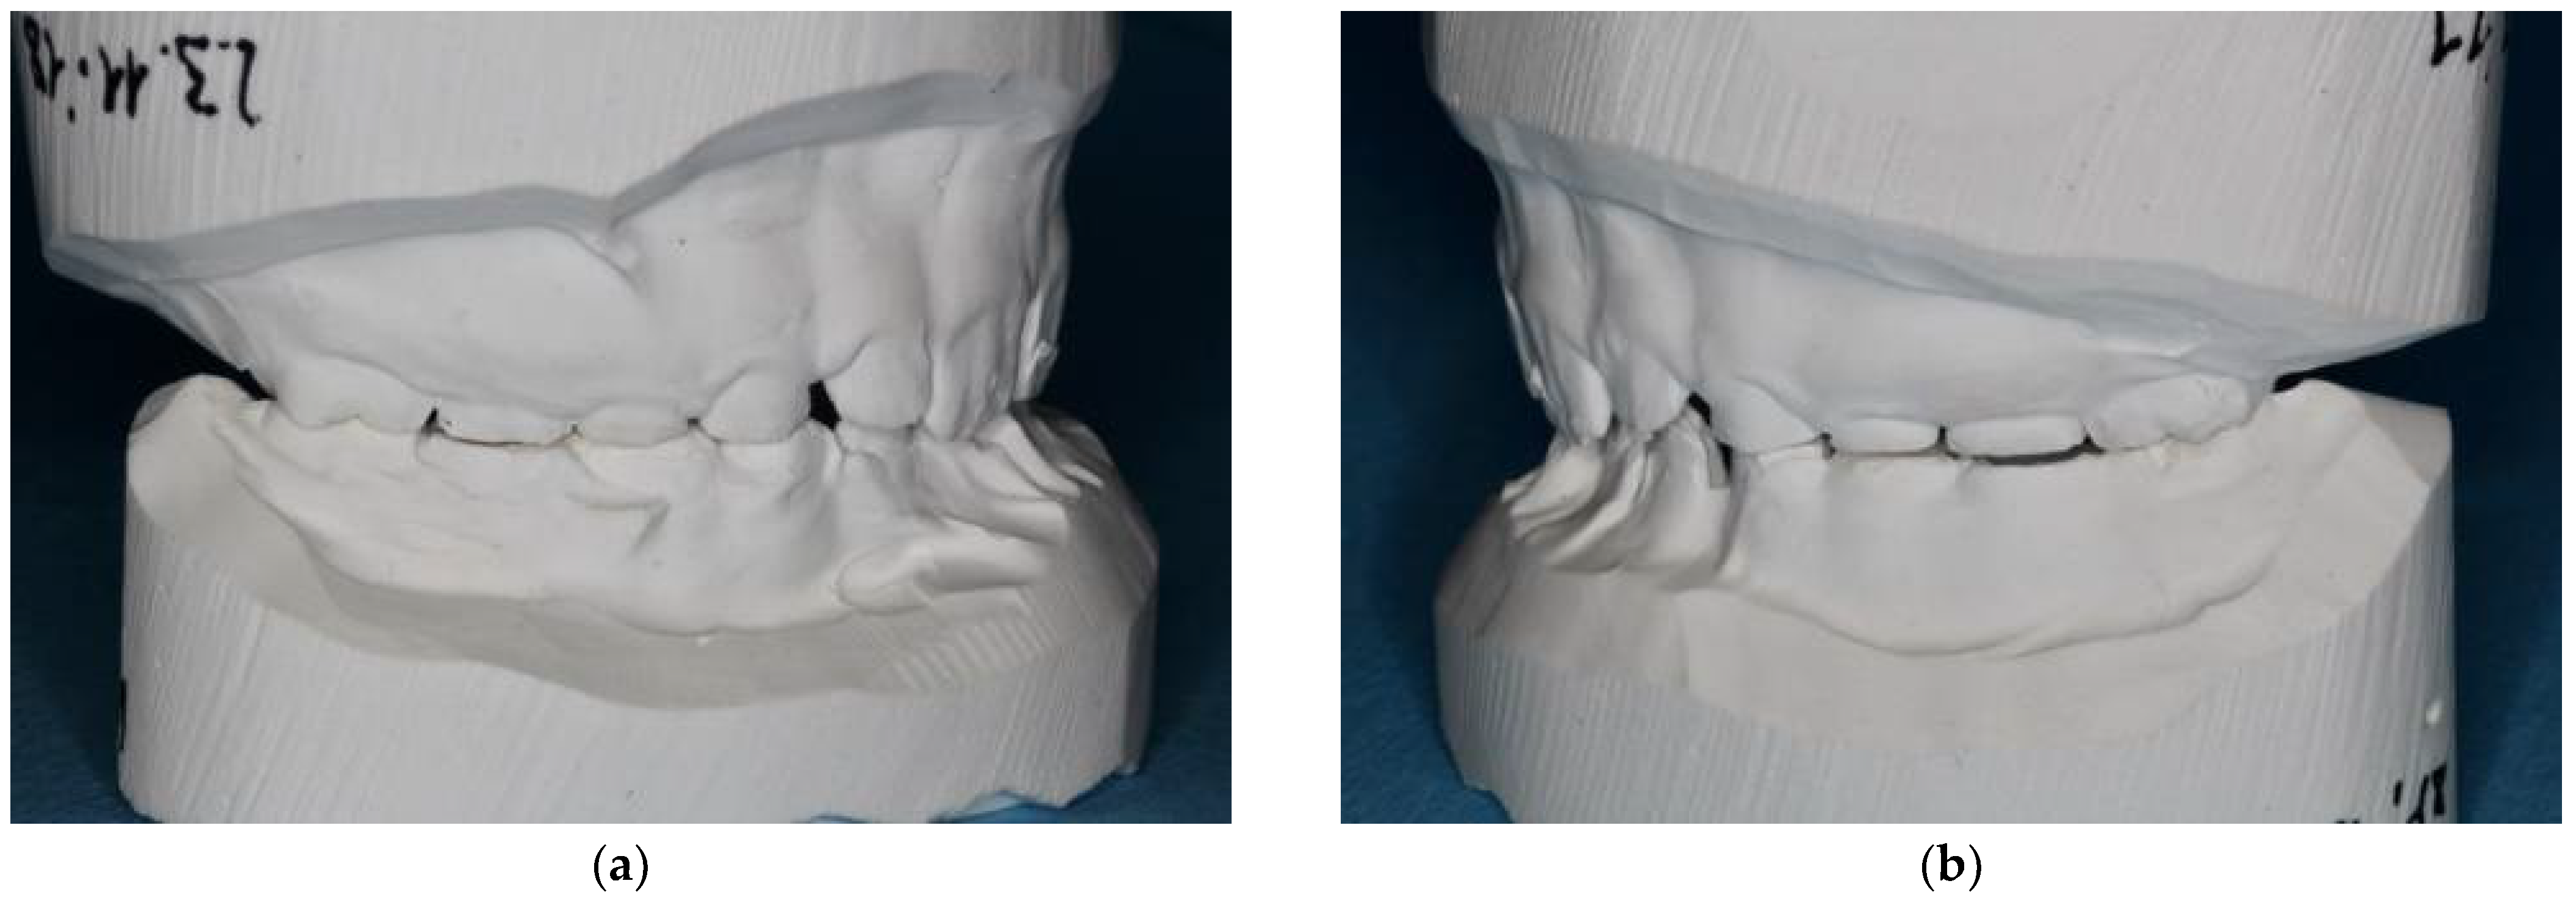

2.2. Case Report: Permanent Dentition